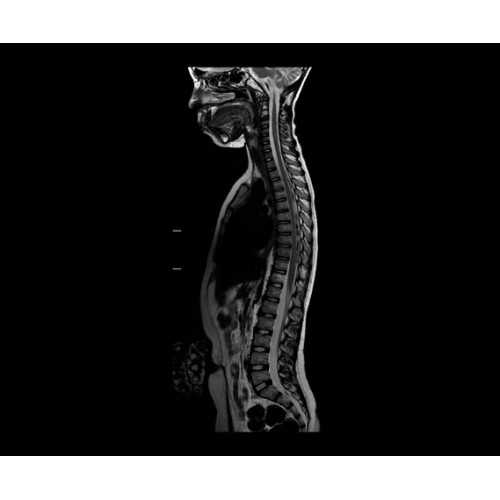

• NeuroWorks — универсальное решение для визуализации анатомии головного мозга, позвоночника, сосудов и периферических нервов с четкой дифференциацией тканей.

• Digital Surround Technology (DST)— это новая технология объемной оцифровки данных, которая объединяет сигналы от каждого элемента катушки. Прекрасное соотношение сигнал/шум и чувствительность поверхностных катушек в сочетании с превосходной однородностью и высокой проникающей способностью встроенной радиочастотной катушки — все это позволяет создавать качественные изображения не только позвоночника, но и всего тела.